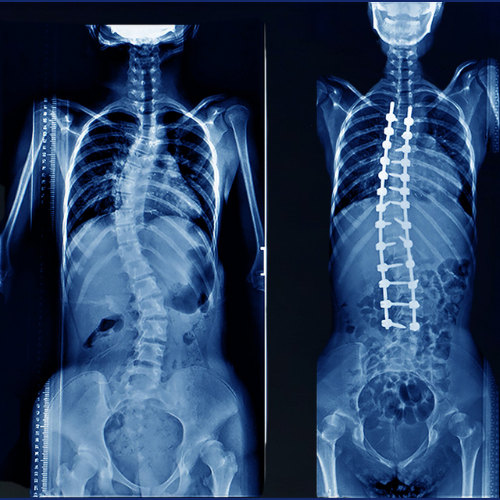

1. Scoliosis & Spinal Deformity Correction

Scoliosis & Spinal Deformity Correction surgery is performed to treat abnormal curvatures of the spine that can cause pain, imbalance, and reduced mobility. The main goal is to straighten the spine, restore proper alignment, and prevent the deformity from worsening. Depending on the severity, techniques such as spinal fusion, rods, screws, or minimally invasive methods may be used. This surgery not only improves posture and appearance but also relieves nerve compression, enhances lung function, and increases overall quality of life. With expert evaluation and modern techniques, patients achieve long-term stability, improved function, and significant pain relief.